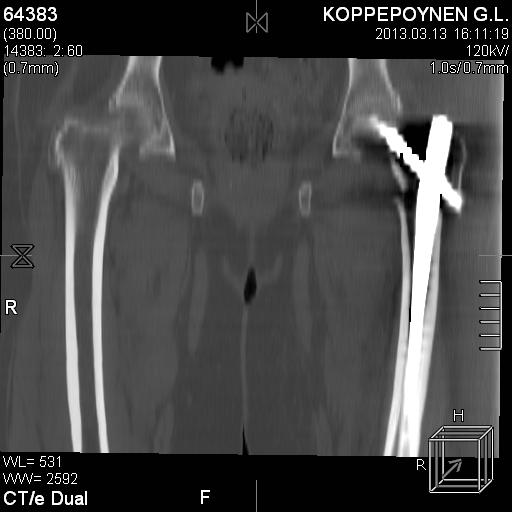

Делали КТ после операции.

|

Отправитель: Alexander Chelnokov 14 Октябрь 2013, 03:21

Непонятно, на какой вопрос с помощью КТ хотели получить ответ? IMHO это было ненужное исследование, все проблемы были видны на обычном снимке. А что на второй проекции? Где аксиальная или профиль?

есть КТ после операции. у пациентки направление введения стержня совпадает с направлением большого вертела, однако большой вертел расколот на 2 отломка. Задний отломок лежит по оси, передний отломом "отошел" и создается впечатление неправильного введения стержня. Динамизации у пациентки не было... Привезут снимки после операции, скину